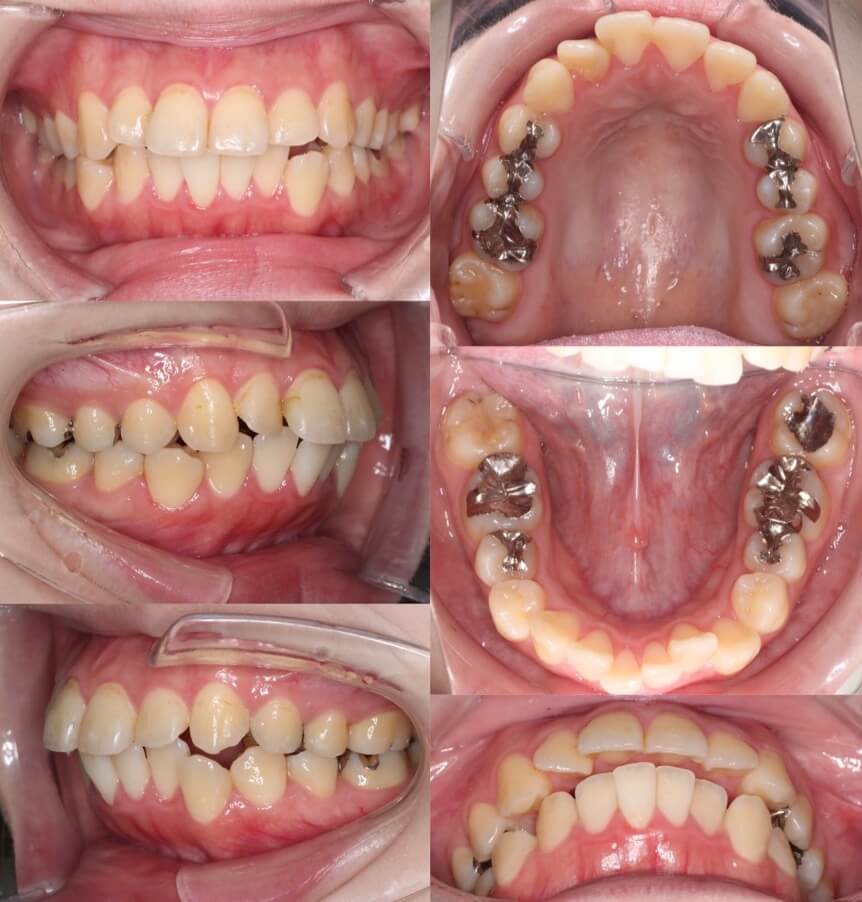

「美容目的にはリスクが伴う」

20代女性・マウスピース型装置・美容改善型

上の前歯の角度もE-lineも悪くはないのですが、患者さんは横顔での口元の突出感を改善したいということで、マウスピース型装置にて上下小臼歯抜歯矯正治療を行いました。美容目的要素が強くなるため、ほうれい線が深くなったり、ブラックとライアングルが増えるリスクについては事前によく説明しています。治療結果は前歯の後方移動量に対して横顔の変化量は少なめとなり、ちょうど良い形になりました。

<症例概要> 難易度:★★★☆☆

主訴:出っ歯・横顔の突出

年齢・性別:30代女性

住まい:千葉県船橋市

症状:軽度叢生・下顎前歯唇側傾斜

治療方針:抜歯空隙の閉鎖(中等度固定)

治療装置:マウスピース型矯正装置(アライナー装置)

抜歯:上下左右4番(計4本)

治療期間:1年6か月

アライナー枚数:47+30ステージ

リテーナー:上下クリアタイプ+フィックスタイプ

治療費用:990,000(税込)

代表的副作用:痛み・治療後の後戻り・歯根吸収・歯髄壊死・歯肉退縮